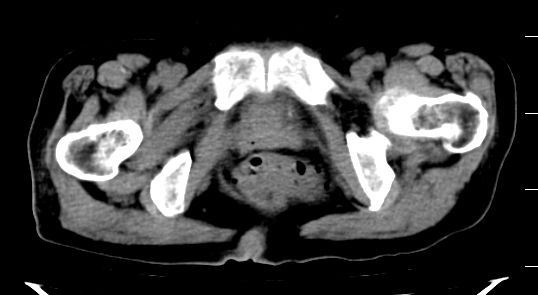

考虑膀胱癌可能性大伴双侧输尿管下端扩张.

1.膀胱后壁见不规则致密影,占位?膀胱内凝血块?建议俯卧位扫描、膀胱镜检查.

2.双侧输尿管下段扩张.

膀胱三角区不规整软组织改变,双侧输尿管扩张,所以占位性病变肯定首先考虑,建议改变体位扫描除外游离血块影,但老年人出血原因一定要查明。

1.膀胱后壁见不规则致密影,随体位改变,为膀胱内凝血块;

2.双侧输尿管下段扩张.输屎管结石可能大。建议作进一步检查。

双侧输尿管下端扩张,并膀胱内血凝块 输尿管下端结石